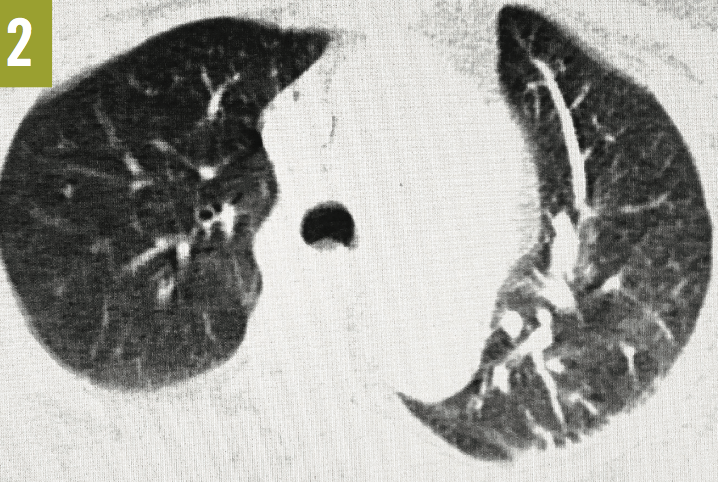

Venous duplex ultrasonography of the left leg confirmed the presence of deep-vein thrombosis. Computed tomography angiography (CTA) of the chest showed a large embolus in the right main pulmonary artery, almost completely occluding the lumen of the vessel (Figure 1). A few peripheral emboli were present in the left lung, as well. Perfusion to the entire right lung was markedly diminished, and there was a compensatory increase in the perfusion of the left lung (Figures 2 and 3). The radiographic findings were consistent with the Westermark sign.

Figure 2: Axial CTA of the chest also showed severe hypovascularity of the right lung with a compensatory increase in the vascularity of the left lung (the Westermark sign).